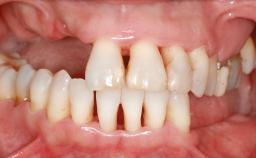

Ridge Preservation and Implant Placement for a Fixed Dental Prosthesis After a Car Accident

It is well known to clinicians that any removal of teeth will, over time, cause the dimensions of the alveolar ridge to be reduced by resorption of the bundle bone and by changes related to external modeling. This development is particularly evident in the crestal region with its thin buccal bone that consists of bundle bone almost entirely. The facial bone will rapidly resorb as blood supply from the periodontal ligament gets disrupted (Araújo and Lindhe 2005). There is no reason why traumatic tooth loss should not have the same consequences. It takes more than achieving implant osseointegration for a treatment outcome to be considered successful. No deficiency of bone or soft tissue is acceptable when an ideal esthetic outcome is the goal. Several articles (Sanz and coworkers 2011; Vignoletti and coworkers 2011) have reported on techniques of improving the alveolar ridge for implant treatment, notably focusing on protecting tissues from resorption.

Soft Tissue Anatomy Intact Defective

Bone Volume Horizontally and vertically sufficient Horizontally deficient Deficient vertically or deficient vertically AND horizontally